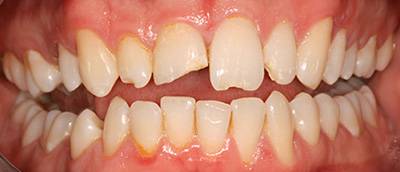

11. eset

27 éves páciensünk egész életében rettegett a fogorvosi beavatkozásoktól. Az összes foga elszuvasodott. A legkárosodottabb fogak gyökérkezelése és a szuvasodásainak megszűntetése után 26 fémkerámia koronát kapott a páciens. Erre a kezelésre is nagyon büszkék vagyunk. 2 hét leforgása alatt sikerült jelentős mértékben javítanunk a páciensünk mosolyán, önbizalmán és mióta velünk talalákozott, már a fogászati kezelésektől sem fél annyira!